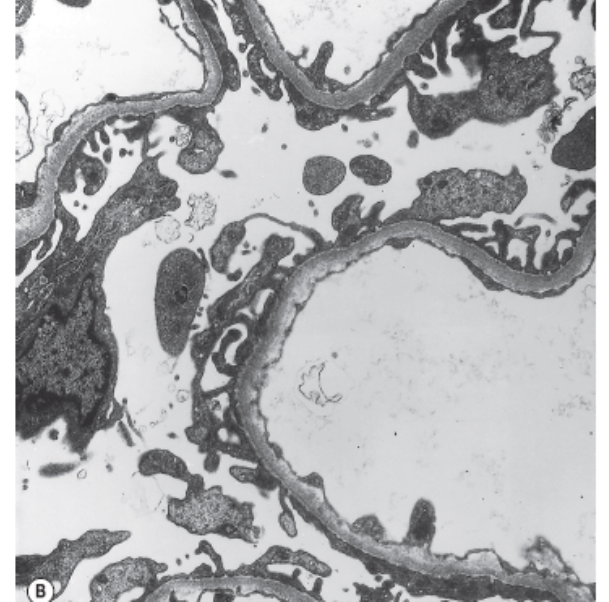

The Clinical Nephrology Section studies various kidney diseases, including membranous nephropathy and focal segmental glomerulosclerosis. The goal of our research is to better understand the evolution and outcomes of these kidney diseases and find treatments that may be more effective and less toxic.

Research Images